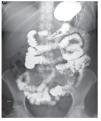

Mujer de 47 años, con antecedentes familiares de carcinoma gástrico, diabetes mellitus tipo 2 e hipertensión arterial sistémica así como antecedentes personales de estreñimiento grave durante la infancia y la juventud; es alérgica a las sulfas. Su padecimiento se inició cuatro semanas antes de su ingreso, al presentar de manera súbita evacuaciones líquidas en número entre ocho a nueve por día, acuosas, sin moco ni sangre, acompañadas de fiebre no cuantificada las primeras 24 a 36 horas del padecimiento, astenia, adinamia, así como artralgias en rodillas y articulaciones interfalángicas distales, pérdida de 6 kg de peso en dos semanas. Luego de la aparición de los primeros síntomas se le prescribió ciprofloxacina, agregándose en el cuarto día de tratamiento quinfamida sin obtener resultados. Luego de 10 días, se modificó el tratamiento a colistín con furazolidona y racecadotrilo, sin mejoría. Acudió a valoración con médico particular, quien indicó metronidazol, salicilato de bismuto y lactobacilos acidófilos por 10 días, así como mesalazina con mejoría parcial sólo de la diarrea. Debido a la mala respuesta al tratamiento, se decidió su hospitalización. A la exploración física destacaba deshidratación moderada de cavidad oral, palidez generalizada de mucosas y tegumentos, sin alteraciones cardiopulmonares, abdomen distendido, con ruidos intestinales aumentados en ritmo e intensidad. En las extremidades inferiores se observó edema en los tobillos y datos de insuficiencia venosa. Se inició protocolo de estudio para diarrea crónica (Tabla 1). Se realizó prueba de D-xilosa en sangre y orina encontrándose estas en límites bajos, el análisis de las heces mostró una evacuación líquida, café, con escasos restos de alimento y moco moderado, leucocitos moderados, fibras musculares escasas y almidón escaso, moco fecal con presencia de leucocitos polimorfonucleares 80%, mononucleares 20% y eritrocitos escasos. El coprocultivo mostró desarrollo de flora normal y el análisis coproparasitoscópico fue negativo. La determinación de antígeno carcinoembrionario y alfafetoproteína fue negativa al igual que las toxina A y B para Clostridium difficile y los anticuerpos antigliadina y antiendomisio. El ultrasonido abdominal fue normal y el tránsito intestinal mostró aumento en el peristaltismo intestinal y engrosamiento de los pliegues a nivel de yeyuno e íleon (Figura 1). Debido a que la paciente continuaba con evacuaciones diarreicas se decidió iniciar manejo antimicrobiano con ciprofloxacino y metronidazol.

¿ Figura 1. Tránsito intestinal; se aprecia engrosamiento de los pliegues a nivel de yeyuno e íleon.